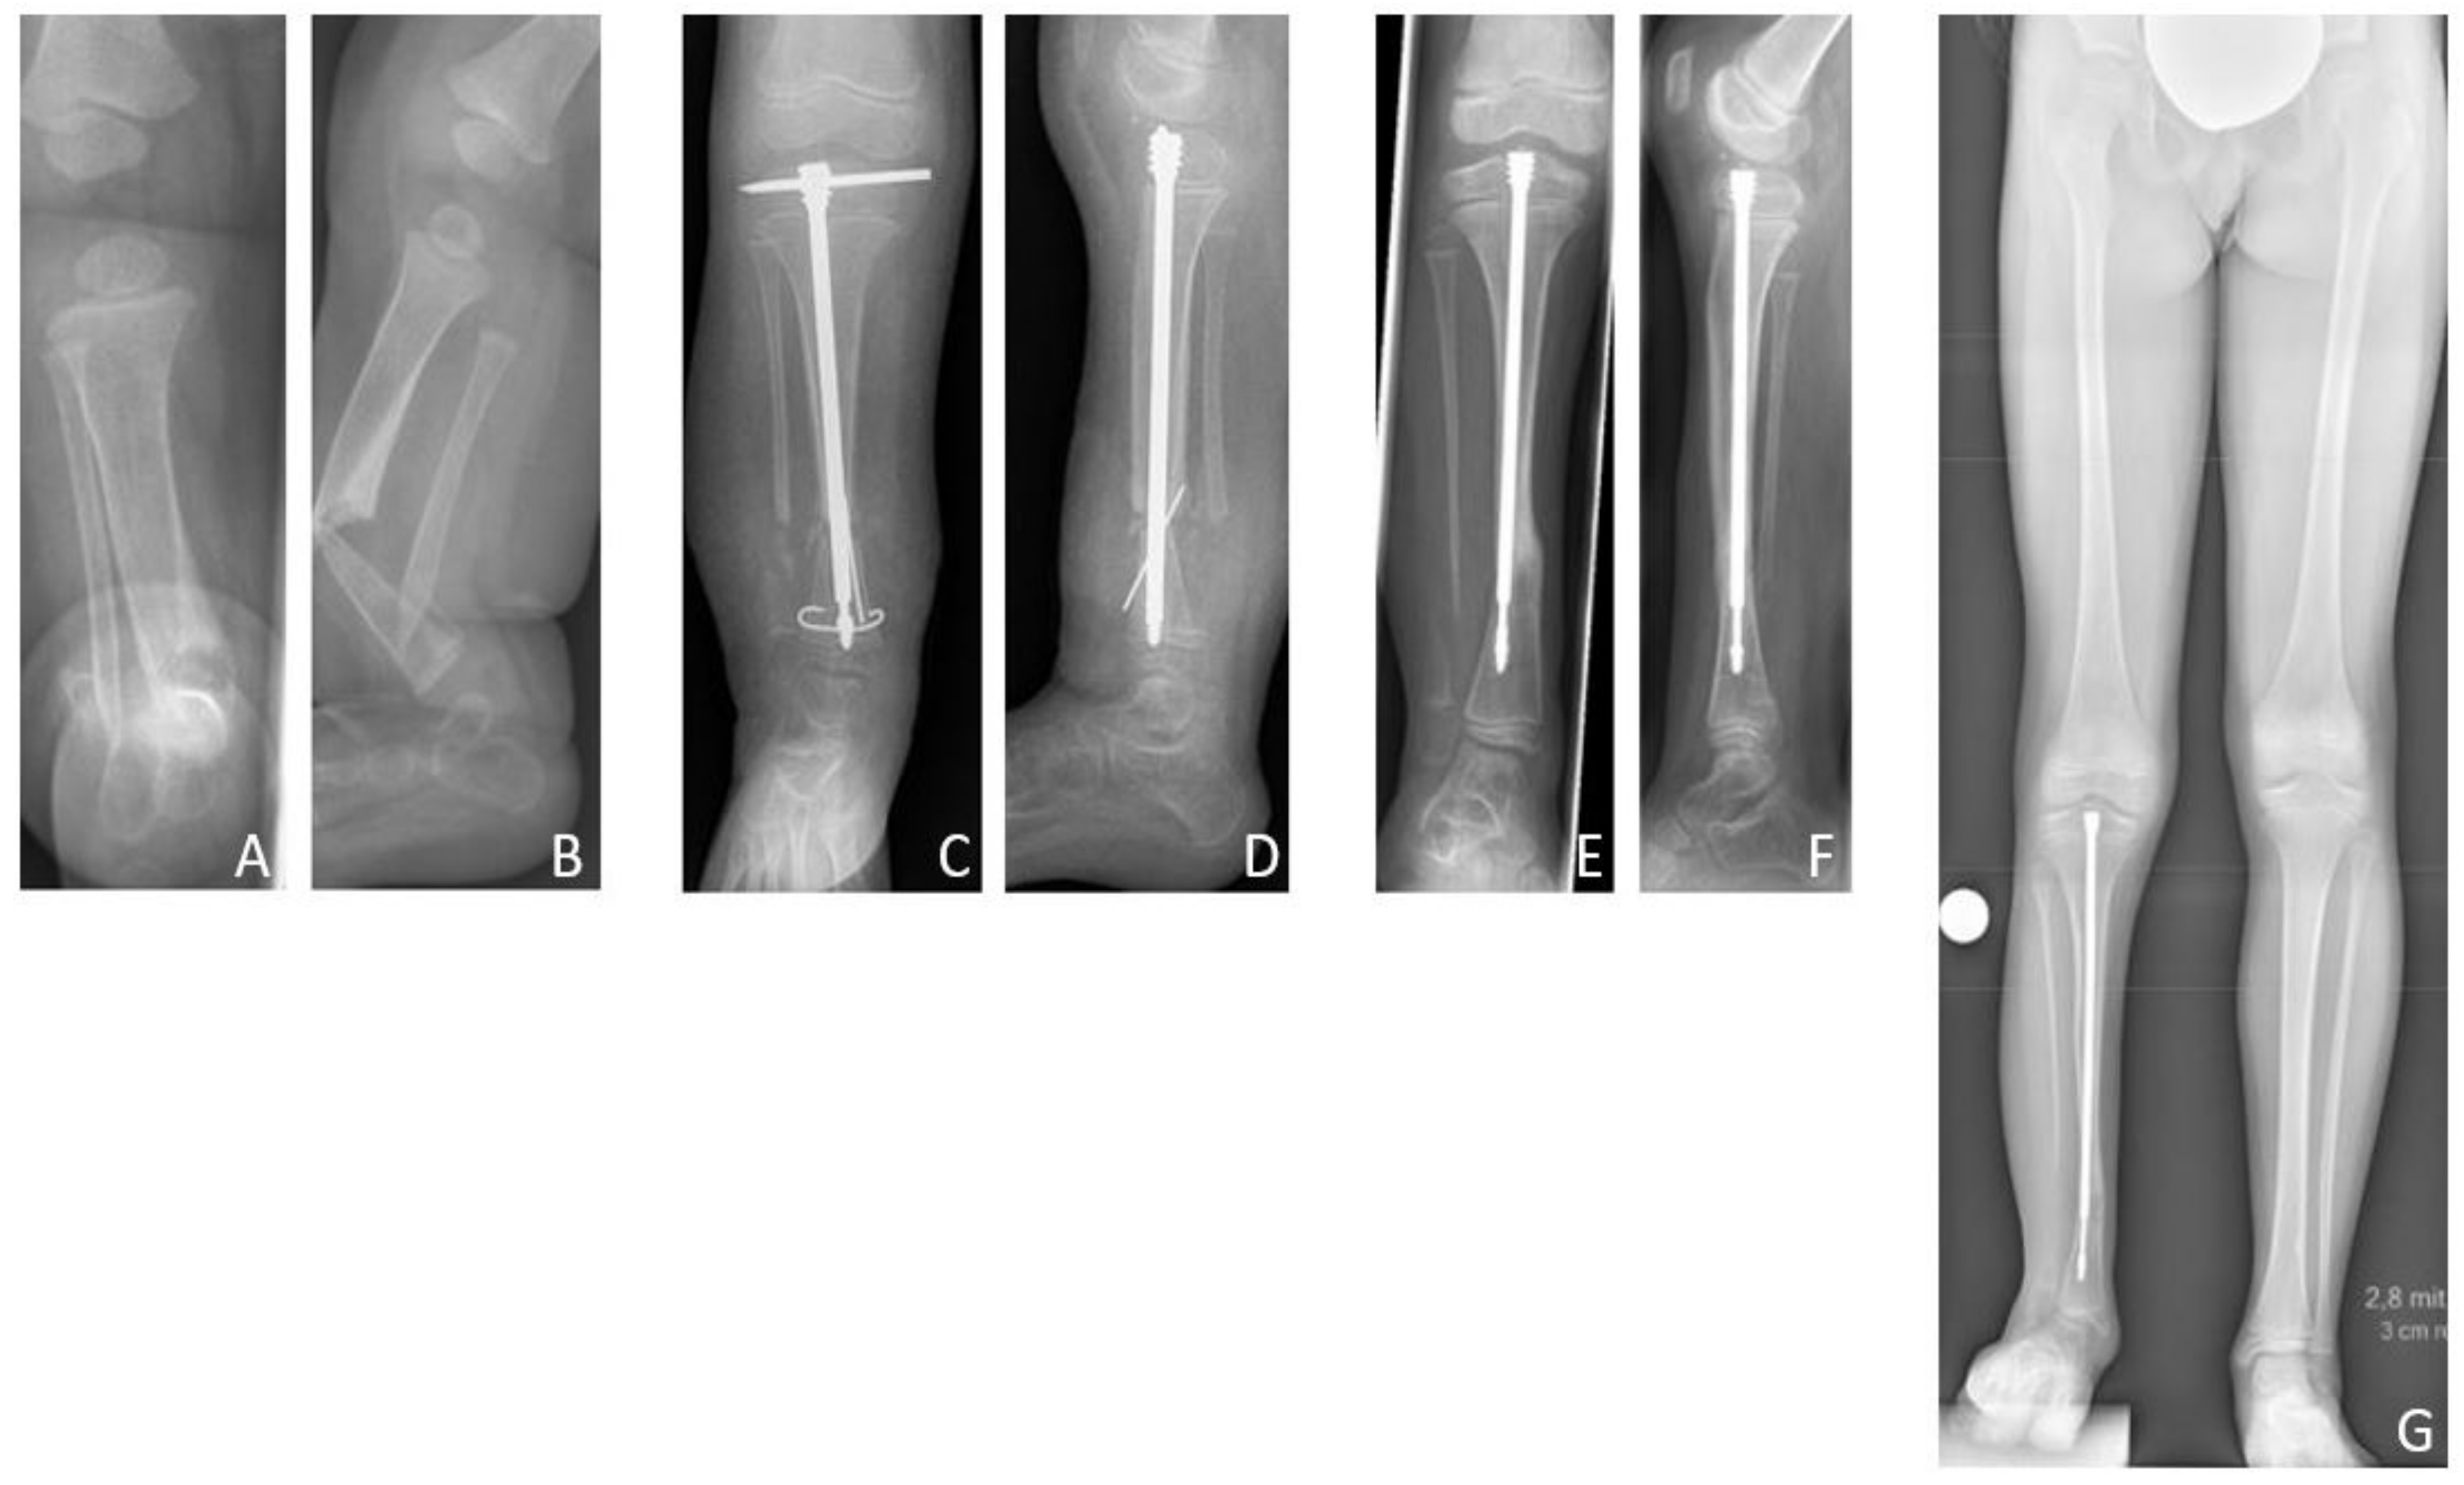

The mean age at first surgery was 7.1 (2.8–14.2) years. Excision of the pseudarthrosis and acute compression before intramedullary stabilization was performed in two cases, while three patients solely received intramedullary nailing for stabilization of the pseudarthrosis site. Four patients (80%) were treated with a Fassier-Duval telescoping nail, and one patient (20%) with a TRIGENTM intramedullary nail. Postoperatively a cast was applied for six weeks. Primary bone union was achieved in three patients (60% primary bone union rate). Excision of the pseudarthrosis had been performed in one of the two cases of failed primary bone union. There were no refractures (0% refracture rate), thus the long-term bone union rate was also 60%. Both patients who failed to achieve primary bone union neither achieved secondary bone union, and showed persistent pseudarthrosis at the time of last follow-up.

According to the modified Johnston criteria, three results were grade 1 and two grade 3 (Figure 8).

Figure 8. Results Group C. Six-month-old female patient with CPT, presenting fracture and pseudarthrosis of the right tibia (A,B). After conservative treatment with orthotic braces, first surgery with resection of the pseudarthrosis and implantation of a Fassier-Duval telescoping nail was performed at the age of four years (C,D). Radiologically, consolidation was achieved 14 months postoperatively (E,F). The patient received subsequent distraction osteogenesis for lengthening of 5 cm when six years old. At the time of last follow-up at the age of nine years she presented a residual LLD of 3.4 cm and ankle valgus (G). (a.p. and lateral views.).